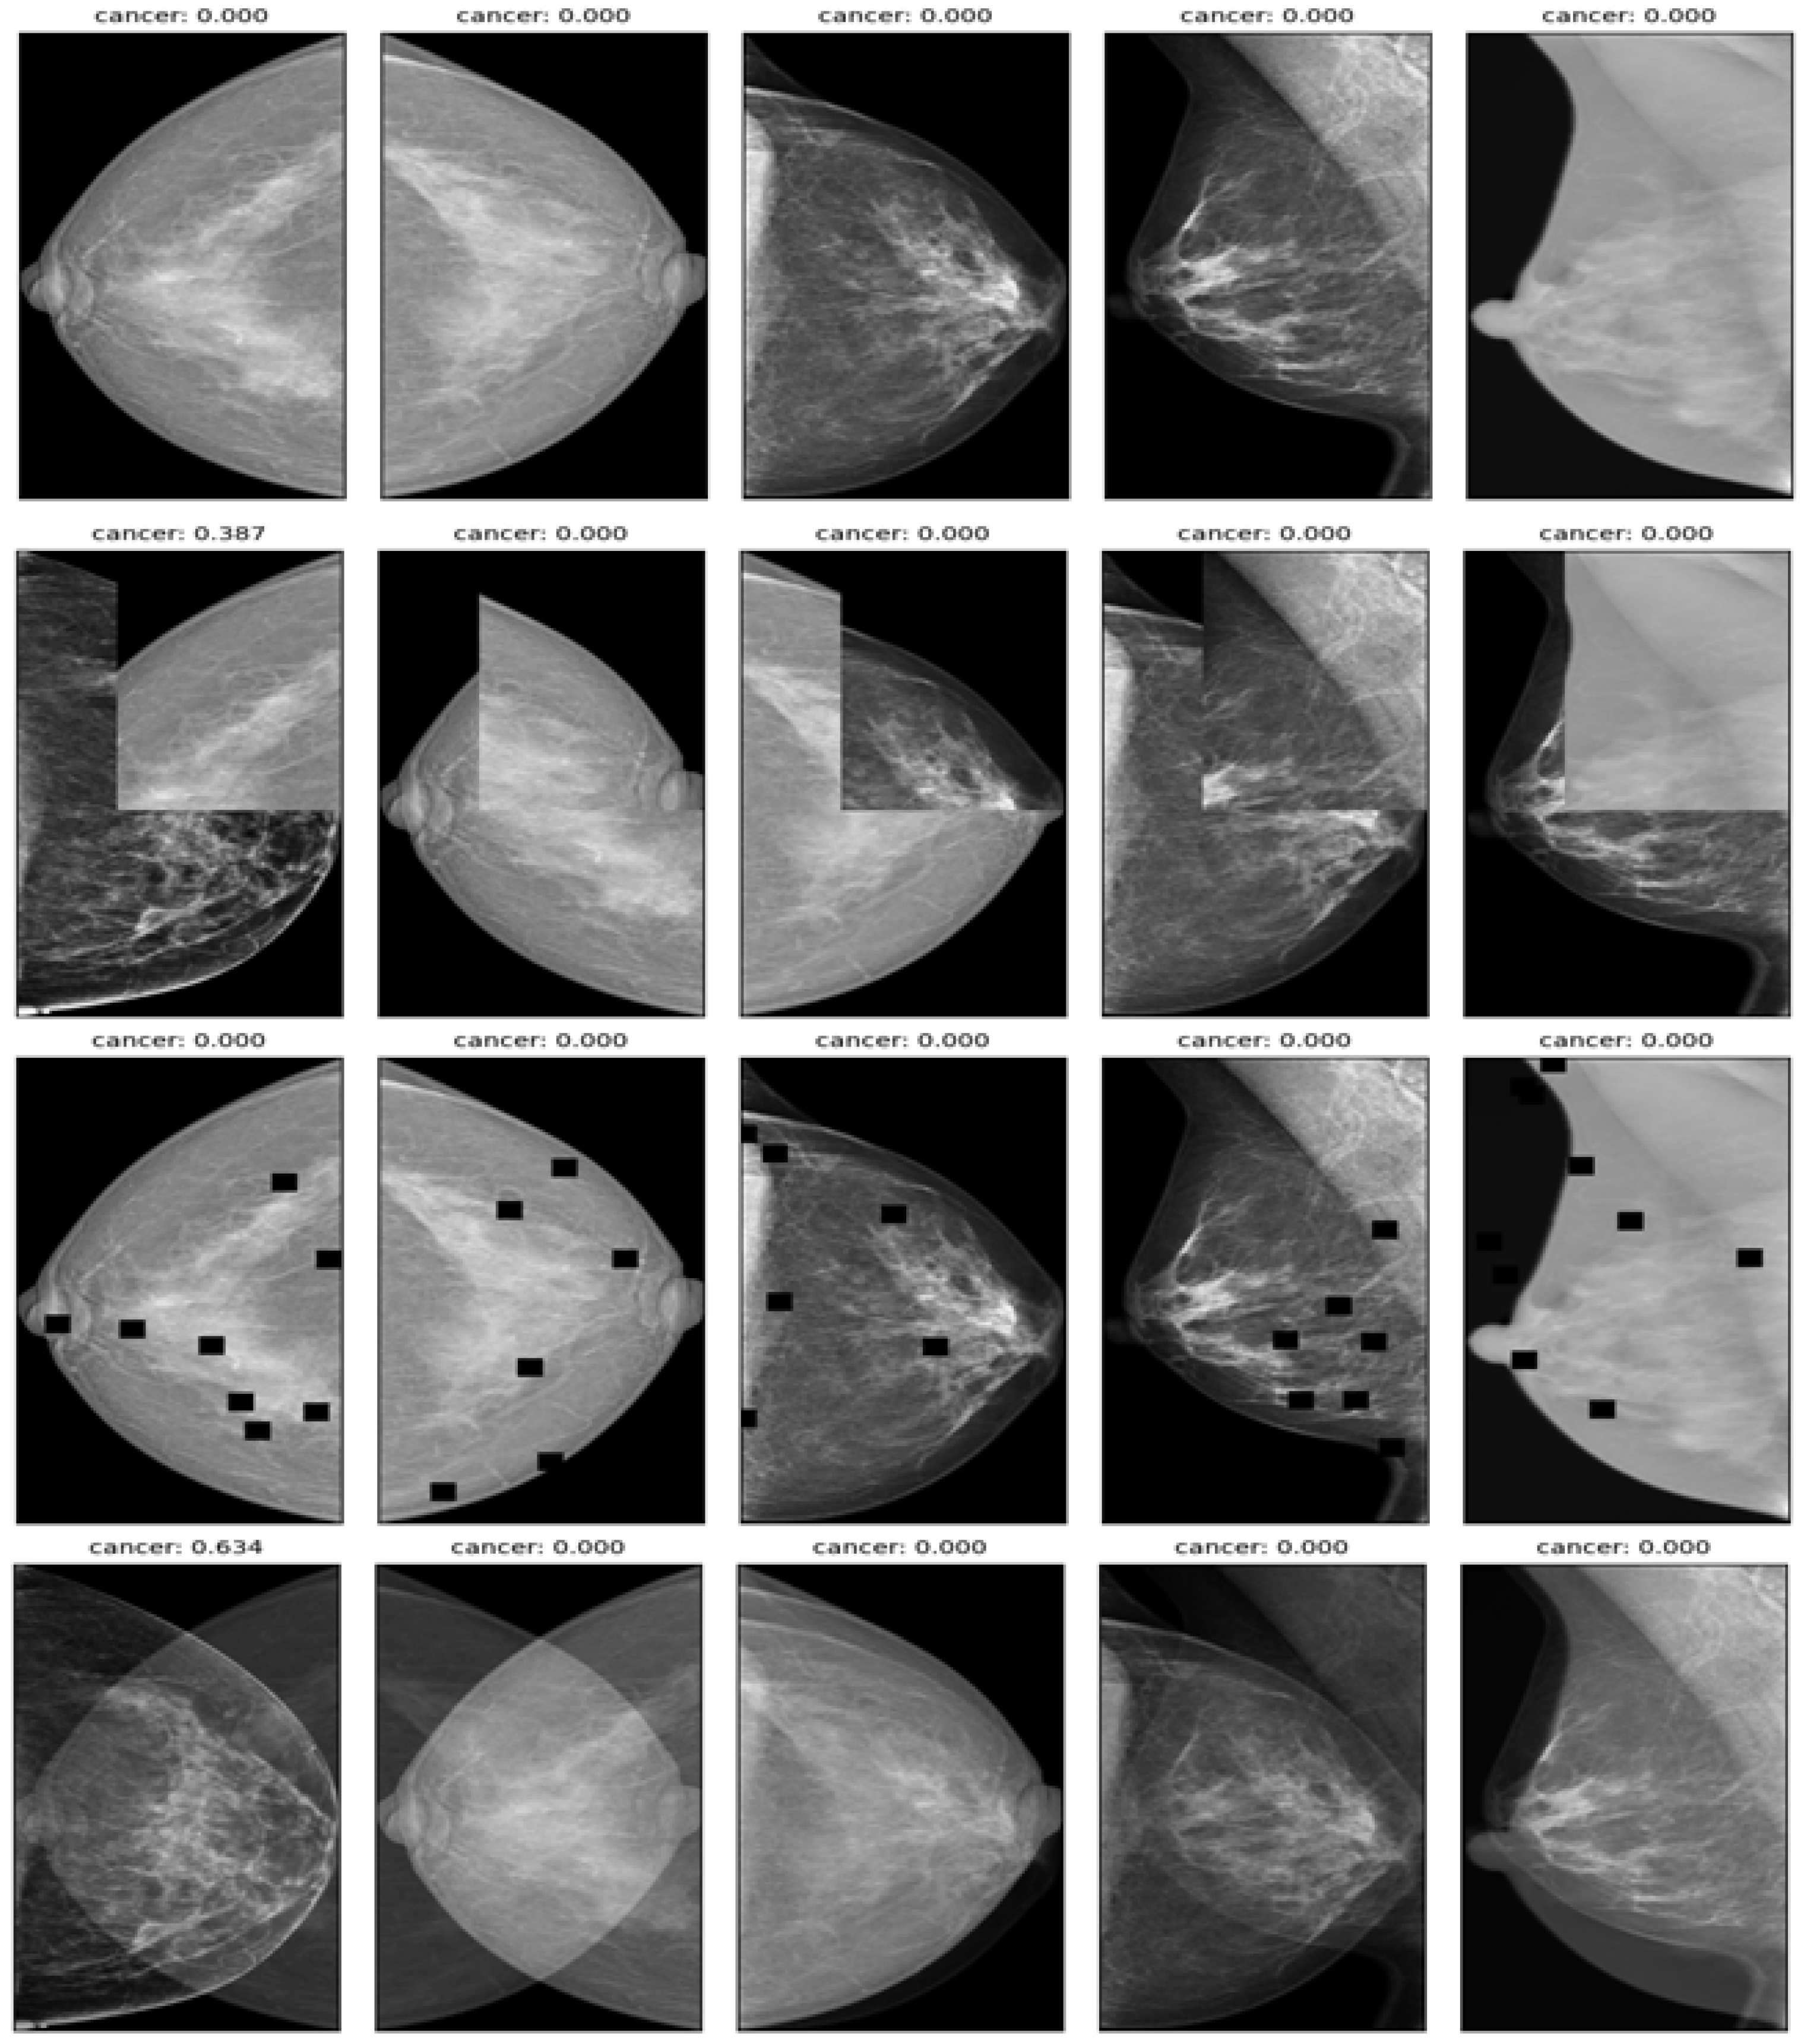

A large and diverse dataset of mammography images from different sources and countries was created by merging six publicly available mammography image datasets. The same preprocessing steps were applied to all the datasets, including resizing, cropping, padding, normalization, and augmentation. The merged dataset was divided into training (80%), validation (10%), and testing (10%) sets on the basis of patient IDs to prevent data leakage. Table 1 presents the summary statistics of the merged dataset. Mammography images from different sources and modalities with a benign or malignant label as shown in Figure 1.

Figure 1.

Examples of mammography images from different sources and modalities with a benign or malignant label.

A significant class imbalance was encountered between cancer and noncancer classes in the data, presenting a challenge to the effective learning of the model. Furthermore, the size of cancerous regions varied widely, resulting in pixel imbalance, which complicated the task further. Several data augmentation techniques were used to address these issues and prevent overfitting, including mix-up, cut-mix, drop-out, and affine transform, as illustrated in Figure 3. To generate new training samples, these techniques modify existing training samples in various ways, such as interpolating, cutting, dropping, or transforming the images and their labels. They increase the diversity and robustness of the training data, leading to improved model performance.

Figure 3.

Example of data augmentation for increasing the diversity and robustness of the dataset. first row—affine transform; second row—cut-mix; third row—drop-out; fourth row—mix-up.

- Mix up: A technique that generates new training samples by linearly interpolating between two images and their labels. This technique can produce high-quality inter-class examples that prevent the model from memorizing the training distribution and improve its generalization ability.

- Cut-mix: A technique that generates new training samples by randomly cutting out patches from two images, pasting them together, and assigning the labels according to the area ratio of the patches. This technique can also produce interclass examples that enhance the model’s robustness to occlusion and localization errors.

- Drop-out: A technique randomly drops out units in a neural network layer during training to prevent overfitting. This technique can decrease the co-adaptation of features and increase the diversity of feature representations.

- Affine transform: A technique that applies geometric transformations such as scaling, rotation, translation, and shearing to the images. This technique can increase the invariance of the model to geometric variations and improve its performance on unseen images.